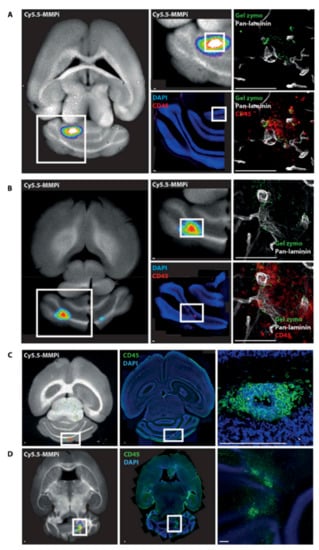

- Gerwien, H.; Hermann, S.; Zhang, X.; Korpos, E.; Song, J.; Kopka, K.; Faust, A.; Wenning, C.; Gross, C.C.; Honold, L.; et al. Imaging matrix metalloproteinase activity in multiple sclerosis as a specific marker of leukocyte penetration of the blood-brain barrier. Sci. Transl. Med. 2016, 8, 364ra152. [Google Scholar] [CrossRef] [PubMed]